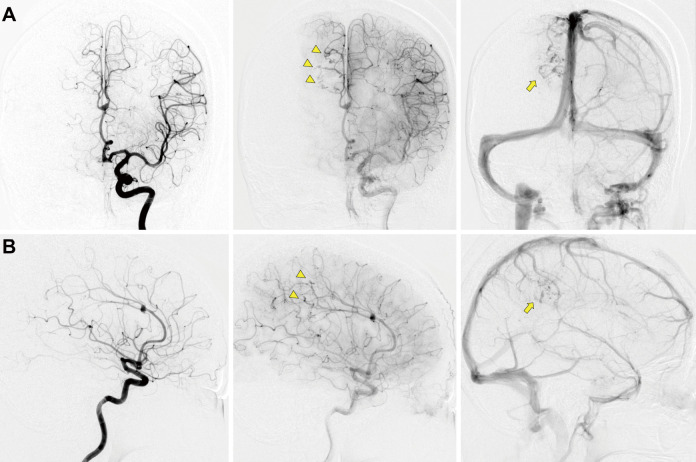

Spontaneous regression of an arteriovenous malformation (AVM) is a rare condition observed in 0.3%-1.3% of patients with AVMs and is most likely caused by hemorrhagic events. The regression of an unruptured AVM is rarer than that of a ruptured AVM. Moreover, due to its low frequency of occurrence, the etiology and natural course of spontaneous regression of an AVM is still unclear. This is the first report presenting a case of a spontaneous regression of an unruptured AVM caused by a gradual drainer vein thrombosis that was suspected to result from hypercoagulability due to protein S deficiency.